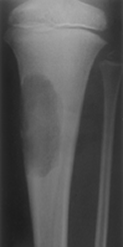

Fig 19. Lesión diafisiaria.

Rx AP. Imagen compatible con encondroma, en la diafisis tibial.